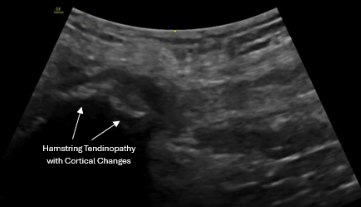

Posterior Hip

• Proximal hamstring tendinopathy

• Ischial region irritation

PRP is commonly performed under real-time ultrasound guidance for gluteal and hamstring tendons to ensure precise placement at the site of pathology.